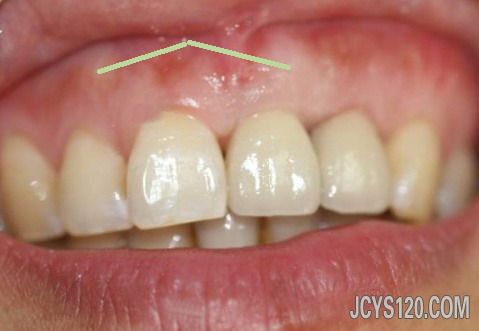

本帖最后由 喜欢 于 2013-3-7 15:38 编辑 牙槽骨是有骨刺的,但在临床上多见有骨刺区有骨尖,局部牙龈有时可见白色(压迫引起),用手按压局部有压痛,既然是牙医说的骨刺,应该由牙医解决,而不是找我们内科医生解决,浮版主说好,3 楼就说的有点过了。 1.消除有碍的骨突:牙齿拔除后由于骨质的吸收不均,常可形成骨尖或骨突。若经过一段时间后仍不消退,且有压痛,或有明显倒凹,妨碍义齿摘戴时,应进行牙槽骨修整,一般在拔牙后1个月左右修整较好。   2.骨性隆突修整术:骨隆突系正常骨骼上的骨性隆起,组织学上与正常骨组织无区别。过大的骨隆突在义齿摘戴时,引起组织破溃疼痛,严重者义齿无法戴入使用。   修复前应有充分的估计和判断,及时施行修整术。骨隆突常发生在:①下颌前磨牙舌侧,一般双侧对称,也可为单侧,其大小不一,也称为下颌隆突;②腭中缝处,呈嵴状隆起,也称为腭隆突;③上颌结节,结节过度增生形成较大的骨性倒凹。对双侧上颌结节肥大的情况,常常只需修整一侧上颌结节,解决妨碍义齿就位的问题即可。